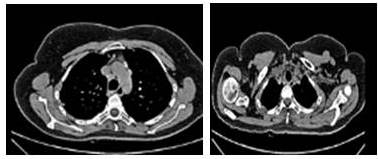

La tomografía de cuello reportó adenopatías sub-mandibulares y submaxilares de 8 mm, glándula tiroidea de aspecto heterogéneo con nódulos calcificados en su interior, adenopatías en el segmento supraclavicular derecho de 8 mm, adenopatías a nivel del mediastino anterosuperior de 1 cm. La TAC de tórax reportó múltiples lesiones nodulares localizadas a nivel intra-parenquimatoso, predominantemente hacia los lóbulos superiores, de 5 mm, sugestivas de metástasis, adenopatías a nivel de mediastino anterosuperior en ventana aortopulmonar, para-aórticas, hiliares de aspecto patológico, midiendo 1,8 cm (Figura 3).